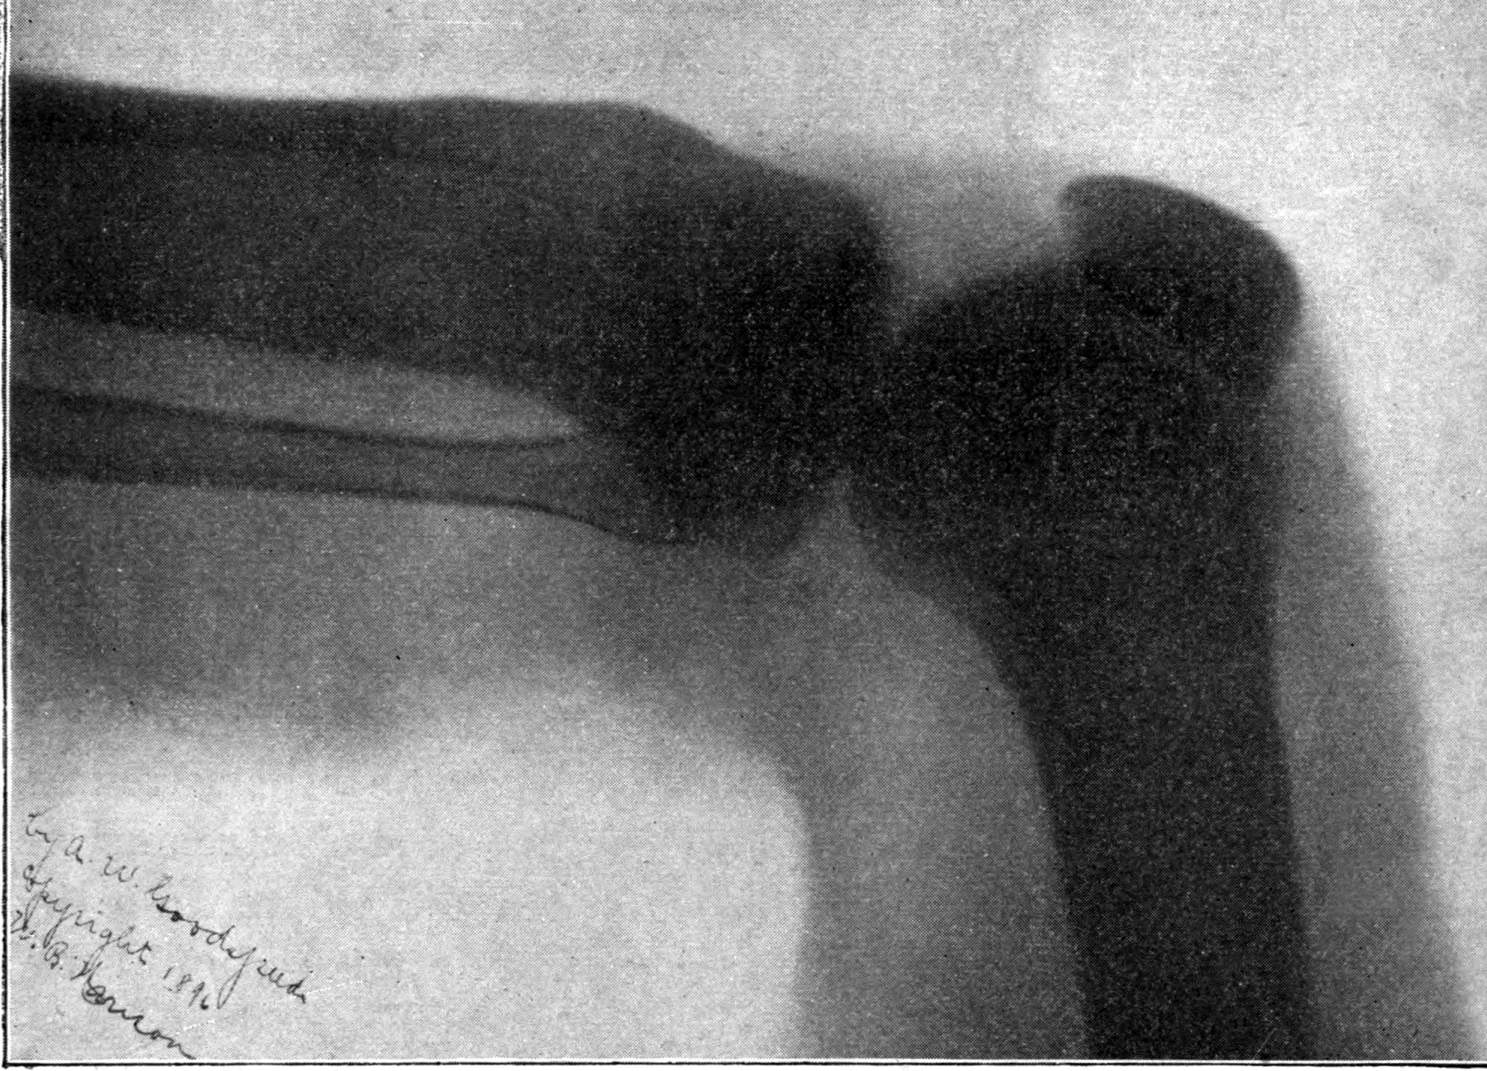

Fig. 2.—Broken Arm, Overlapping.

(Due to defective setting.)

Fig. 3.—Ribs.

Fig. 4.—Knee, Knickerbocker Buttons, Bullet in Femur.

FROM SCIAGRAPHS BY PROF. DAYTON C. MILLER. § 204.